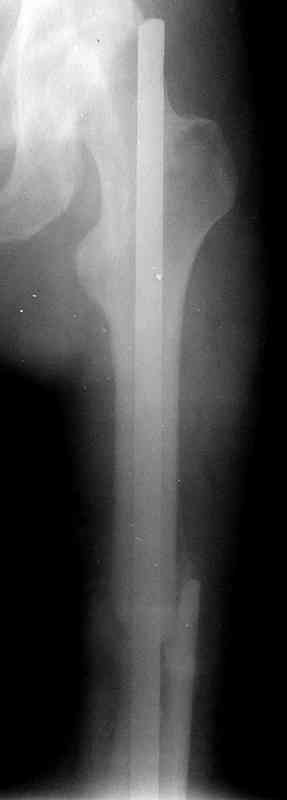

месяцев дистракции укорочение левого бедра удалось полностью устранить. 22.02.00, т.е. через 2 месяца после повторного остеосинтеза, больному произведено дистальное блокирование штифта двумя винтами и демонтирован аппарат Илизарова. В течение 2 недель после операции больной ходил с помощью костылей, потом 2 недели с тростью. Опороспособность и функция оперированной конечности полностью восстановились через 4 недели после операции.

Фиксаторы удалены через 12 месяцев после операции, выполненной по поводу замедленной консолидации перелома бедра с его укорочением.

Спасибо! Истинно мастерская работа. Представляю как счастлив пациент исходом этой истории.

На финальных снимках видно - сращение прям таки железное. Если Вы не устали отвечать, осмелюсь задать еще вопрос - что-то принимал пациент в целях ускорения сроста (кальций, режим питания). Интересны также вопросы восстановления функций конечности - в какой период были рекомендованы группы упражнений для восстановления основных групп мышц?